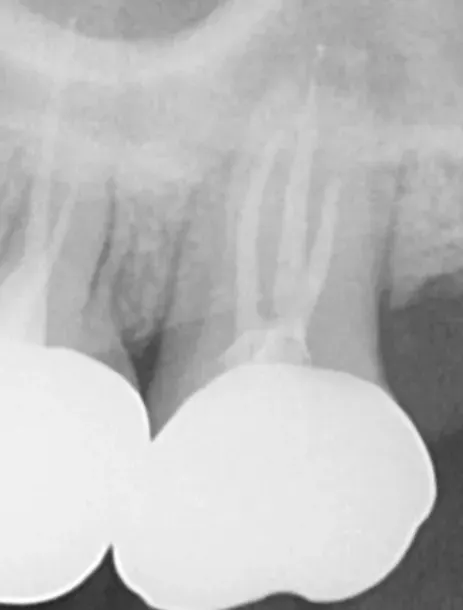

정밀 진단(방사선/치수 검사 등)

충치 제거 및 감염 관리

치수 상태 확인 및 생활치수치료 가능 여부 판단